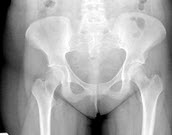

105、单项选择题

女,根据其正常骨盆影像图像,判断其最可能的年龄()

A.28岁左右

B.18岁左右

C.38岁左右

D.78岁左右

E.58岁左右

119、单项选择题

A.54岁左右

B.14岁左右

C.74岁左右

D.34岁左右

E.64岁左右